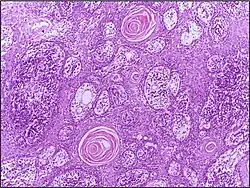

Squamous cell carcinoma of the skin | Well-differentiated squamous cell carcinoma skin showing malignant cells with mild atypia resembling normal squamous epithelial cells with intercellular bridges, individual cell keratinisation and nests of keratin pearls. | Category: Histopathology of squamous cell carcinoma of the skin | Squamous cell carcinoma |

![]() |